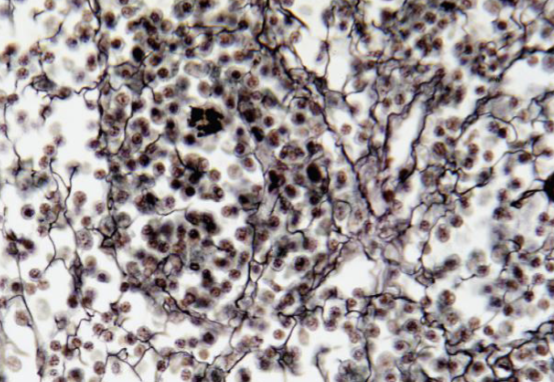

Identifique tipo de tejido conectivo

reticular

Indique sitio anatómico dónde se encuentra

higado